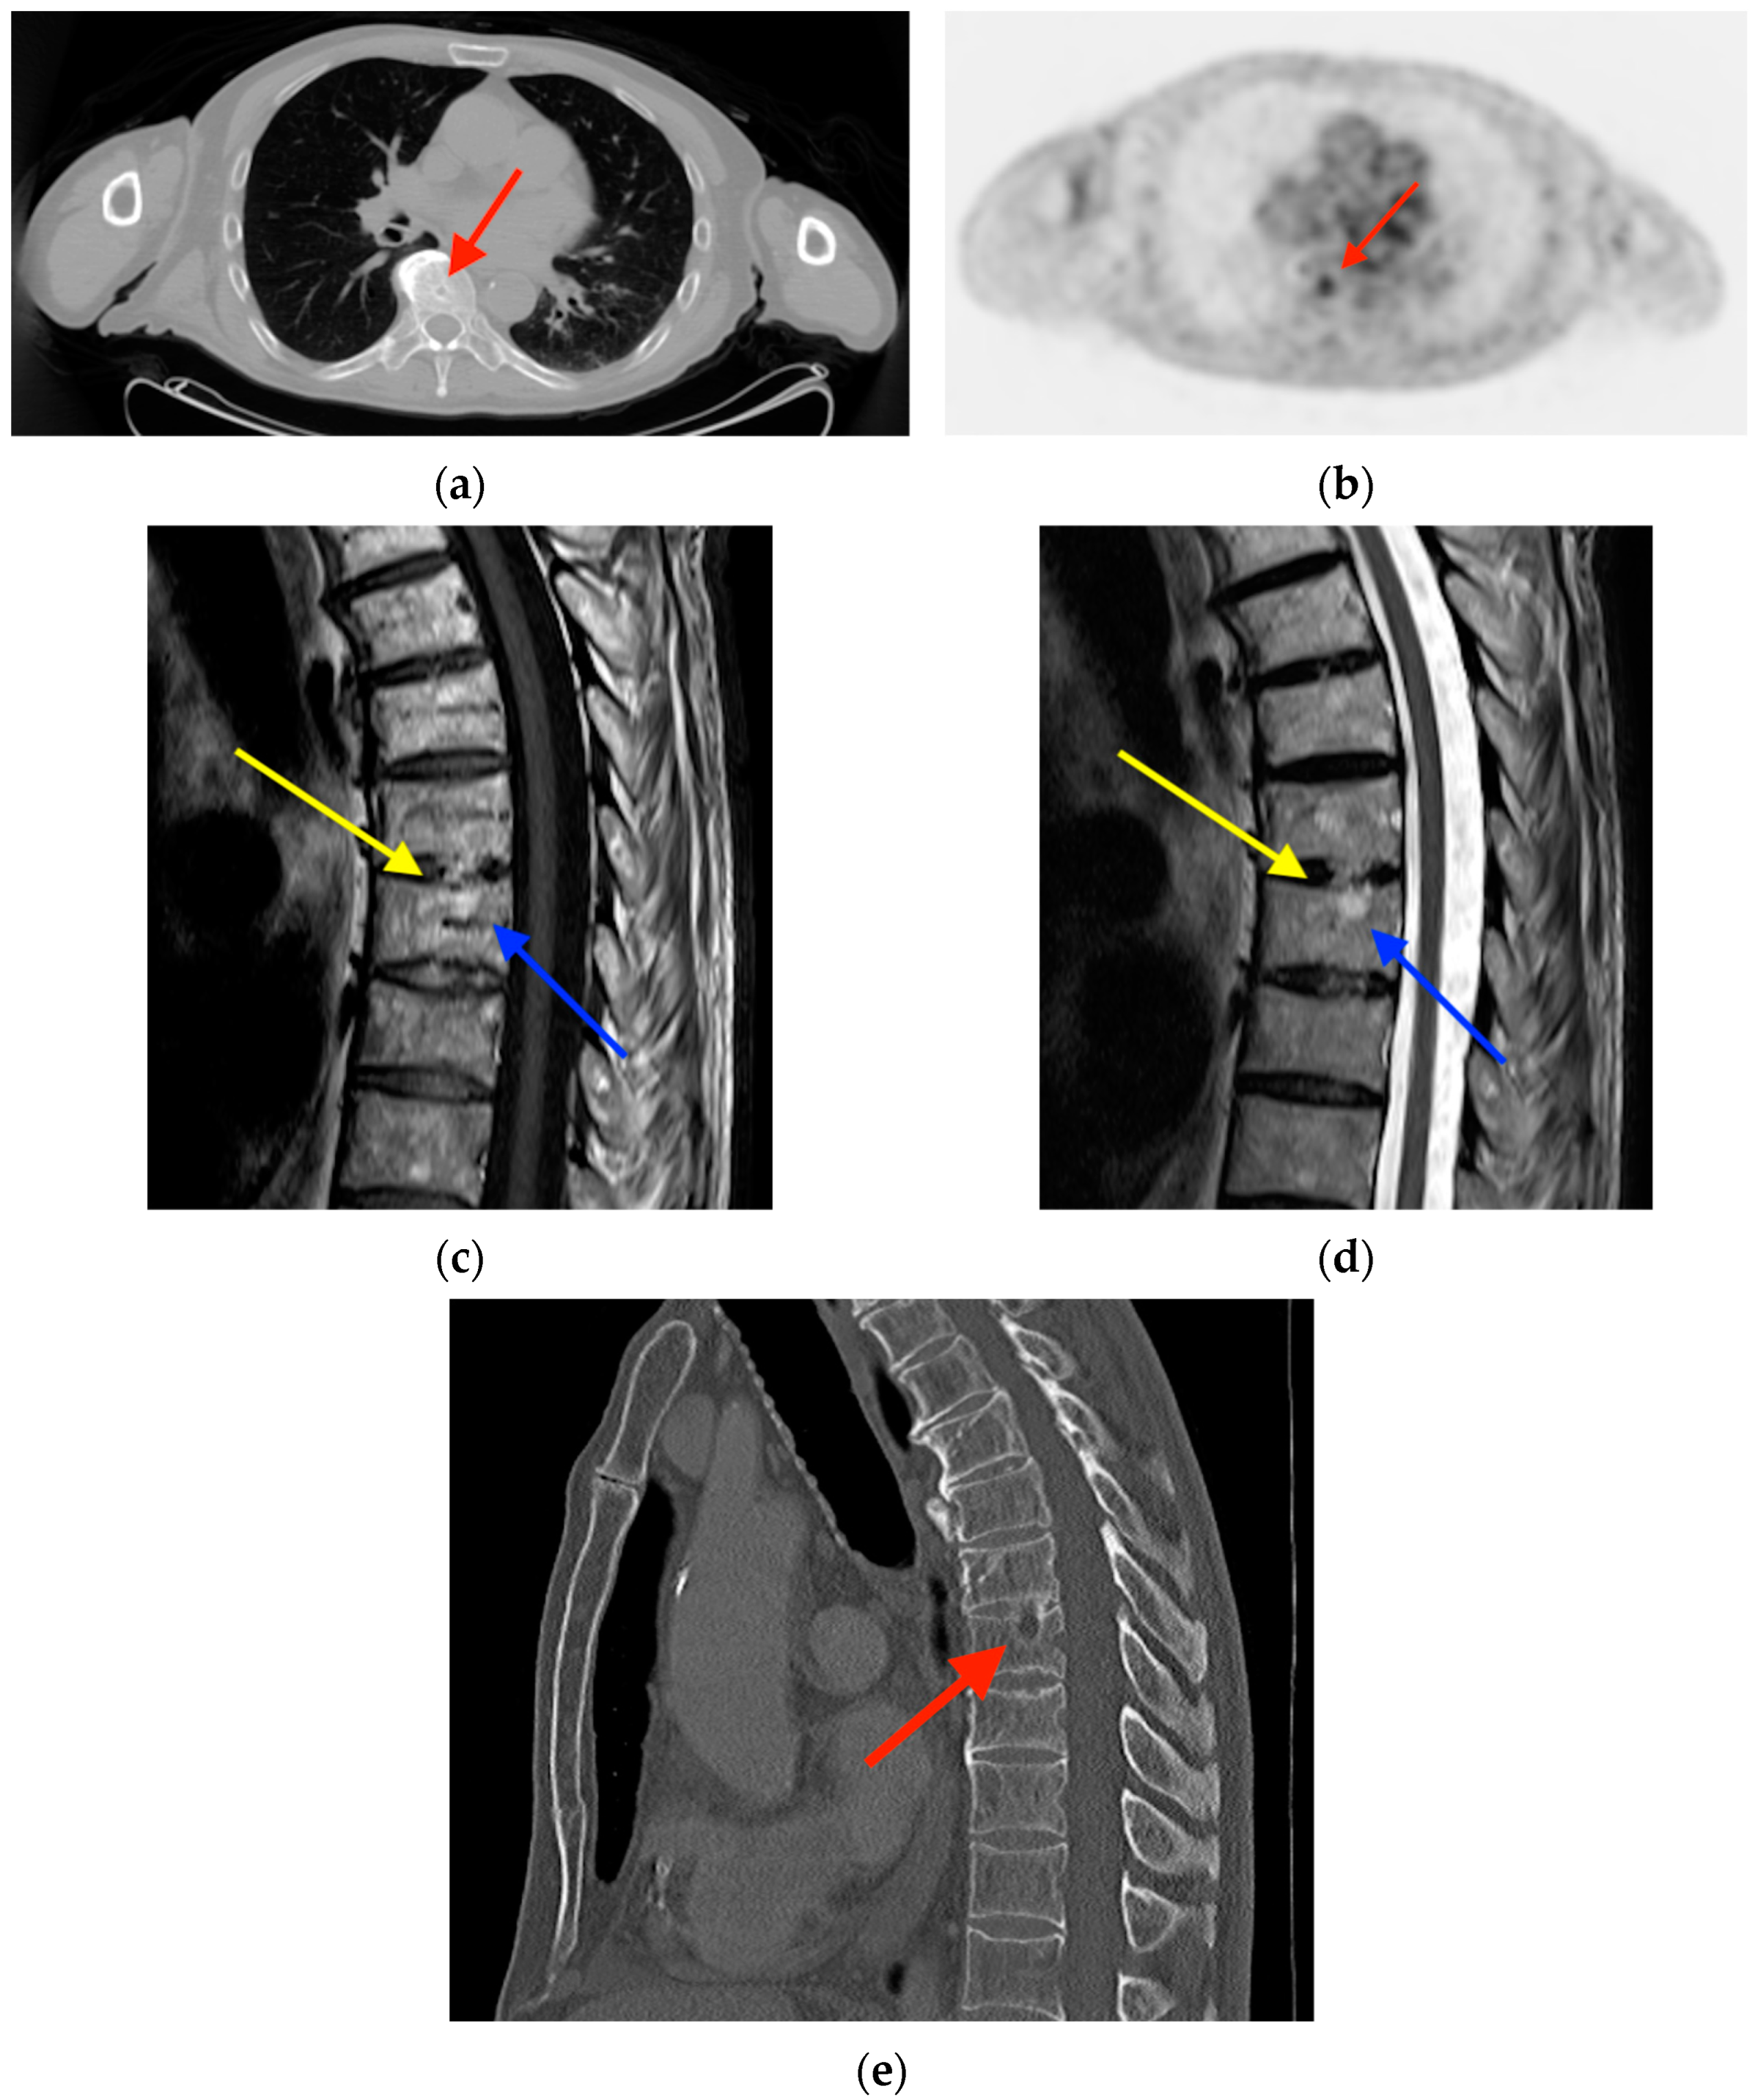

2.4. Schmorl’s Node

- Lin, C.Y.; Chen, H.Y.; Ding, H.J.; Chen, Y.K.; Kao, C.H. Evaluation of Schmorl’s nodes using F-18 FDG PET/CT. Clin. Radiol. 2012, 67, e17–e21. [Google Scholar] [CrossRef] [PubMed]

- Wang, Z.; Ma, D.; Yang, J. 18F-FDG PET/CT can differentiate vertebral metastases from Schmorl’s nodes by distribution characteristics of the 18F-FDG. Hell. J. Nucl. Med. 2016, 19, 241–244. [Google Scholar] [CrossRef]

- Papadakis, G.Z.; Millo, C.; Bagci, U.; Sadowski, S.M.; Stratakis, C.A. Schmorl Nodes Can Cause Increased 68Ga DOTATATE Activity on PET/CT, Mimicking Metastasis in Patients With Neuroendocrine Malignancy. Clin. Nucl. Med. 2016, 41, 249–250. [Google Scholar] [CrossRef] [PubMed][Green Version]